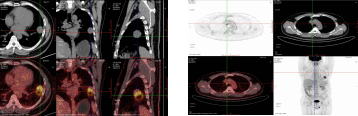

病例概要:患者,男性,50岁,主因“发现左肺上叶占位性病变2月余。”来诊。患者自诉2月前体检胸部CT,发现左肺上叶舌段实性占位,大小约2.5*2.3cm,与胸膜相连,可见分叶、毛刺,恶性可能性大,有咳嗽、咳痰,白痰为主,偶有黄痰,无痰中带血等异常,未采取治疗,定期复查。2周前再次复查胸部ct:左肺上叶占位性病变较前增大,侵犯下叶背段,大小约4.1*3.1cm,考虑肺癌可能。胸外科副主任医师胡晓丹在充分了解患者病情及影像检查后,指示病灶为实性结节且肿物增长过快,需完善全身检查明确有无肿瘤转移可能,后迅速完善全身PET-CT,发现左肺高代谢肿物位于左肺舌段及左下肺内前基底段,病变跨越斜裂胸膜(大小4.6*4.4,SUVmax9.1),恶性可能性大;纵隔、左肺门、右侧内乳区淋巴结转移瘤可能(大者短径1.6cm,SUVmax4.7)。考虑患者淋巴结转移瘤可能性大,需尽快明确病变淋巴结性质,给予经支气管超声内镜纵隔淋巴结穿刺活检术(EBUS-TBNA),胡晓丹会同胸外科医师赵洋乐顺利穿刺4R、4L区、7区、10L淋巴结,术后病理均未见肿瘤细胞,初步考虑淋巴结肿大为良性病变。但为明确肺部占位是否为恶性肿瘤,还需行CT引导下经皮肺病损穿刺活检术明确病变性质,术中操作顺利,无气胸、咯血等异常;术后穿刺病理:(左肺上叶结节)肺脓肿。最终诊断:肺脓肿,在给予2周规范消炎、化痰等治疗后,再次复查胸部CT,病灶大小较前明显缩小(约2.7*3.3cm),实性成分较前明显减少,最终避免了全麻手术切除,顺利出院。

术前PET-CT-左肺占位 纵膈淋巴结肿大